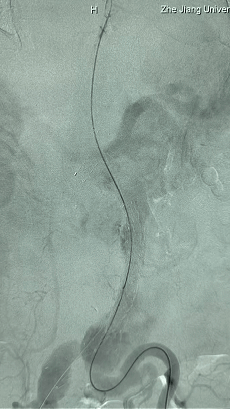

2. 左侧肱动脉入路,超选至降主动脉,更换8F-900mm长鞘,造影提示IV型胸腹主动脉瘤,累及双肾动脉。

3. 经右股动脉导入超硬导丝,然后导入九州ku酷游G-Branch 胸腹主动脉主体覆膜支架TAAA3418120e7i1010 一枚,释放主体支架至内分支打开,然后经左侧肱动脉入路,抓捕预置导丝成功后,将长鞘进入内分支出口处。